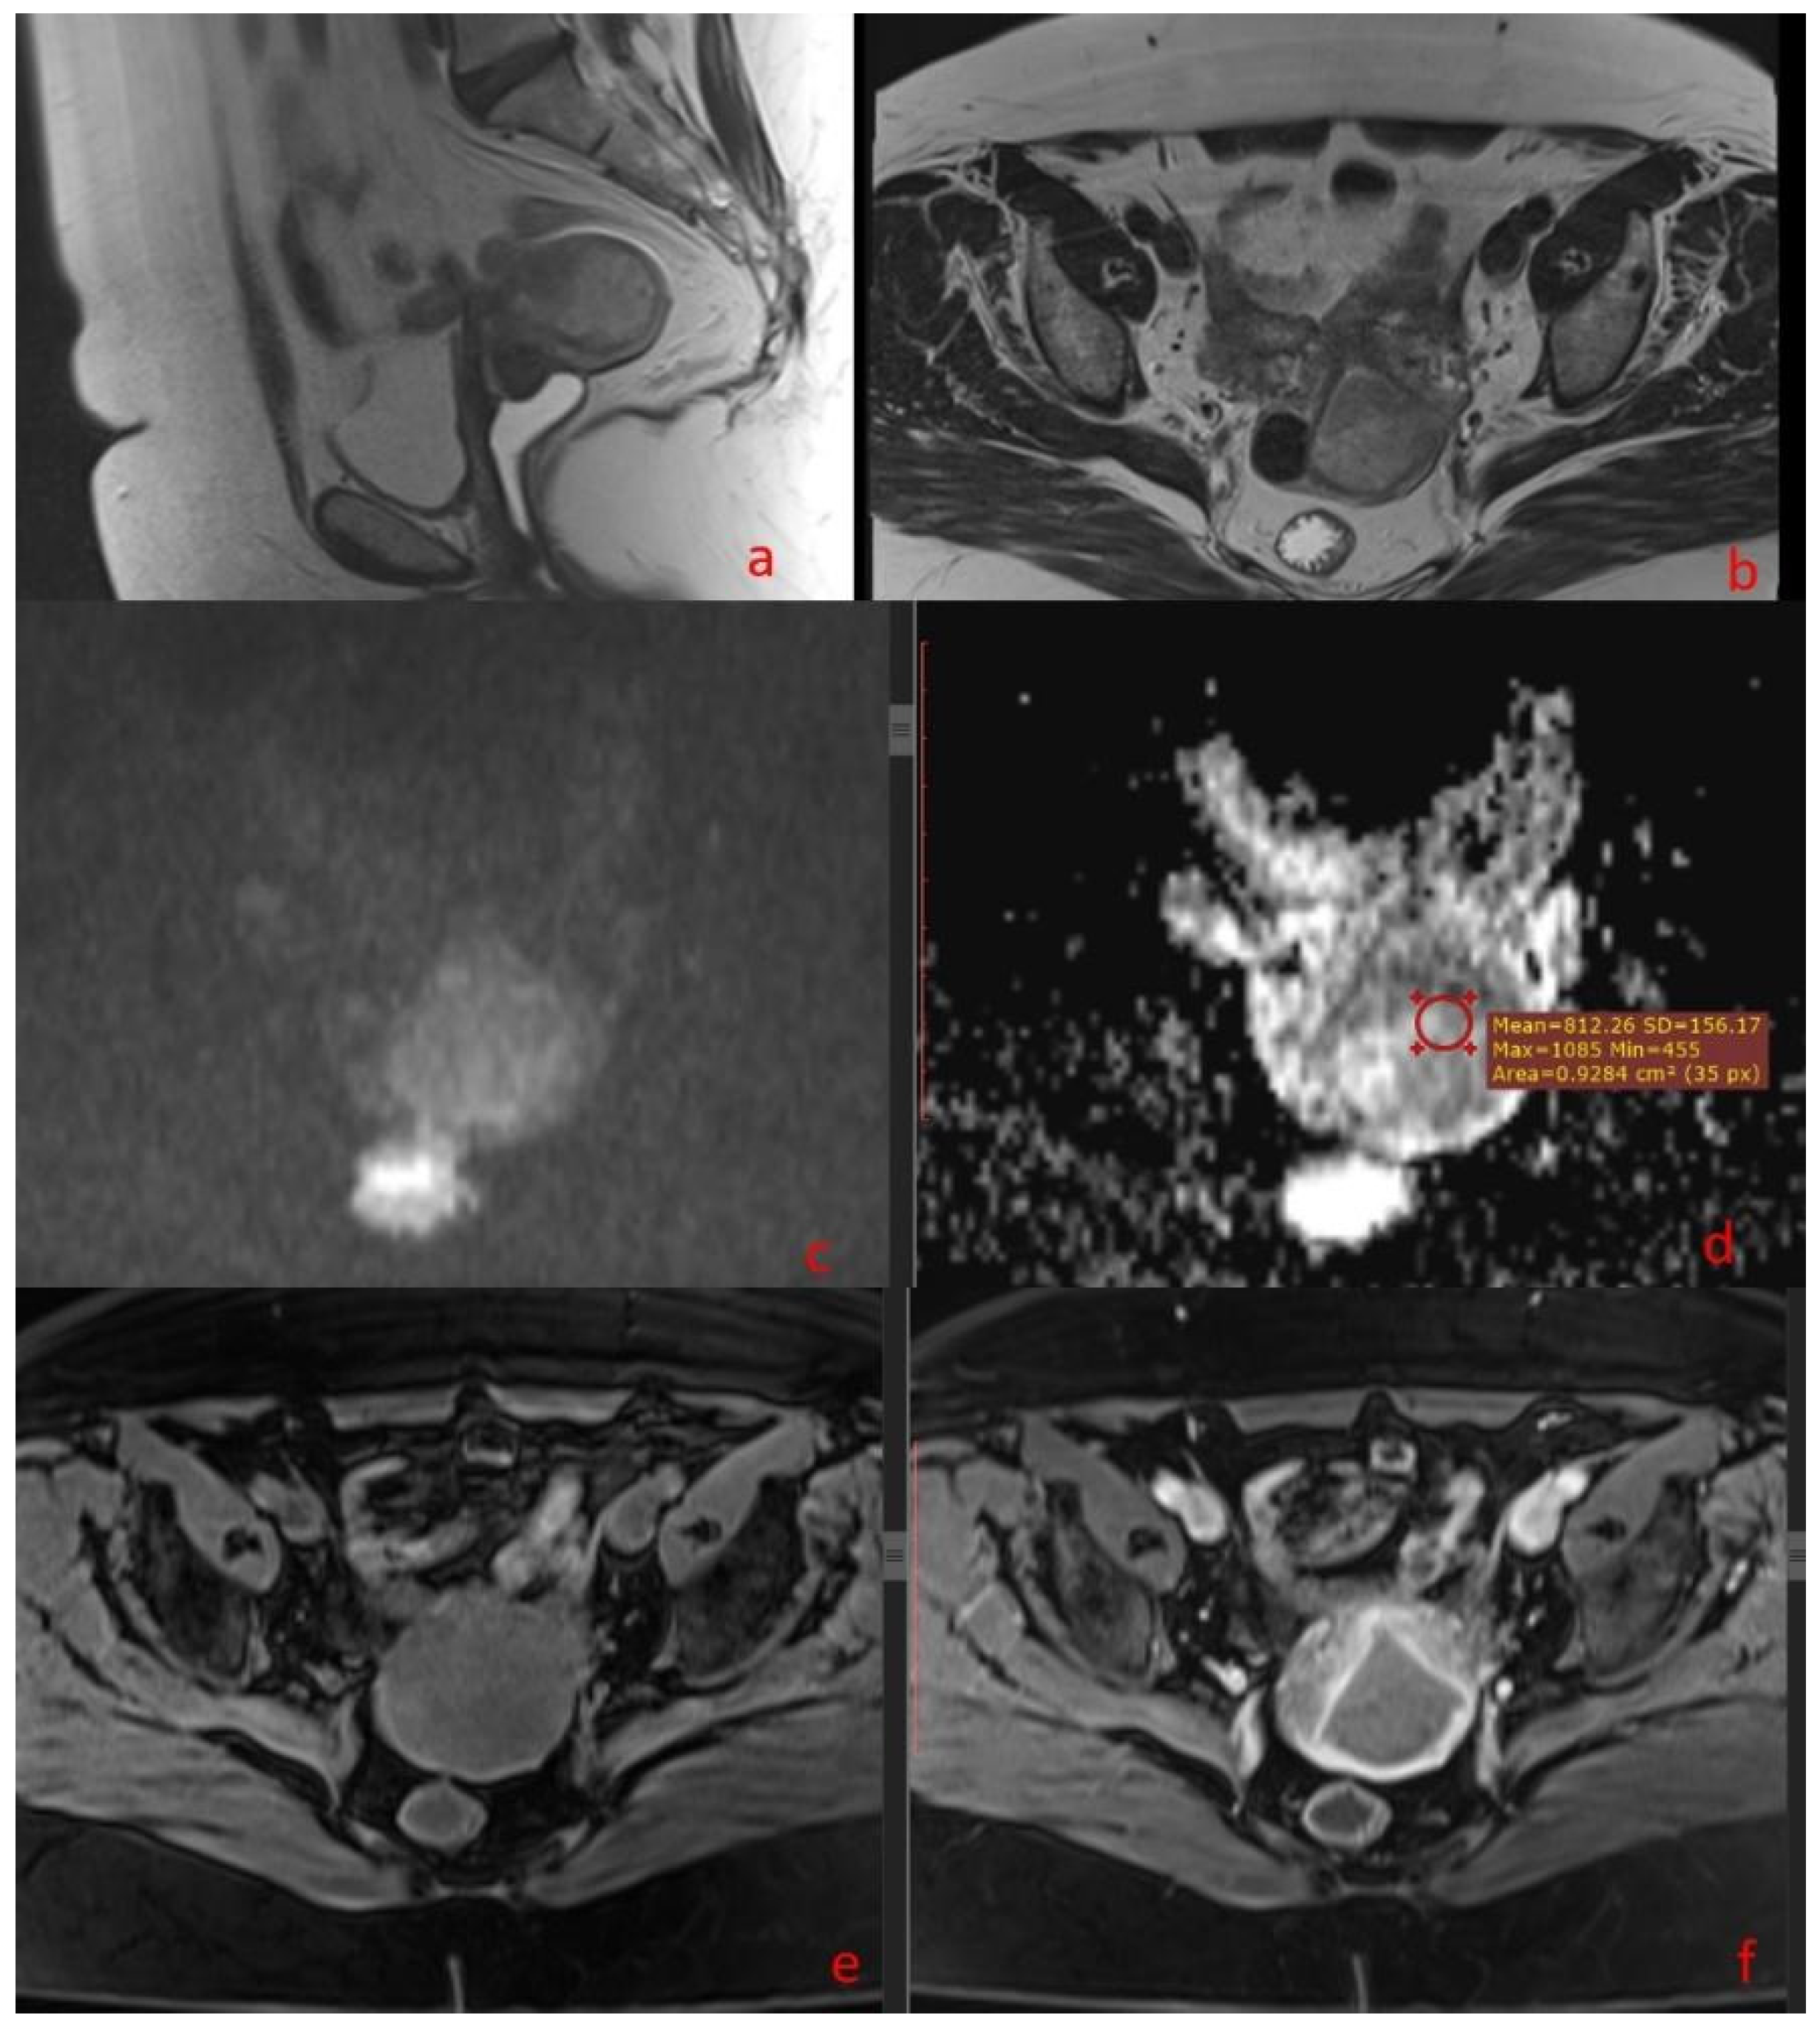

3.2. MRI Findings